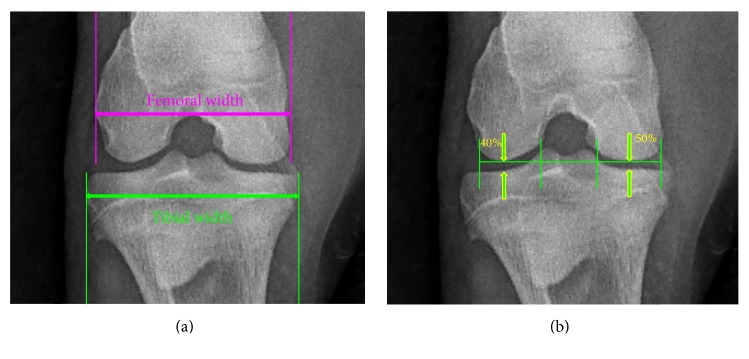

Large animal models of osteoarthritis are a necessary testing ground for FDA approval of human medicine applications. Sheep models have advantages over other available large animals, but development and progression of osteoarthritis in sheep is exceedingly slow, which handicaps progress in development of potential treatments. We combined oblique angle forced exercise to increase stress on the stifle, with surgical destabilization to hasten the development of osteoarthritis in ewes. Methods for early detection of clinical signs included radiography, urine, and serum biomarker assays and gait analysis and ex vivo we used microcomputed tomography and macroscopic joint analysis. Our model was able to produce clinically detectable signs of osteoarthritis in a relatively short period (14 weeks). Changes in bone were highly correlated between microcomputed tomography and radiographic analysis and changes in cartilage correlated well between urinary glycosaminoglycan levels and serum aggrecanase analyses. Exercise improved the negative effects of destabilization in bone but exacerbated the negative effects of destabilization in cartilage. These observations suggest that we may need to consider treatments for bone and cartilage separately. These results represent an improved large animal model of osteoarthritis with rapid onset of disease and superior detection of bone and soft tissue changes.